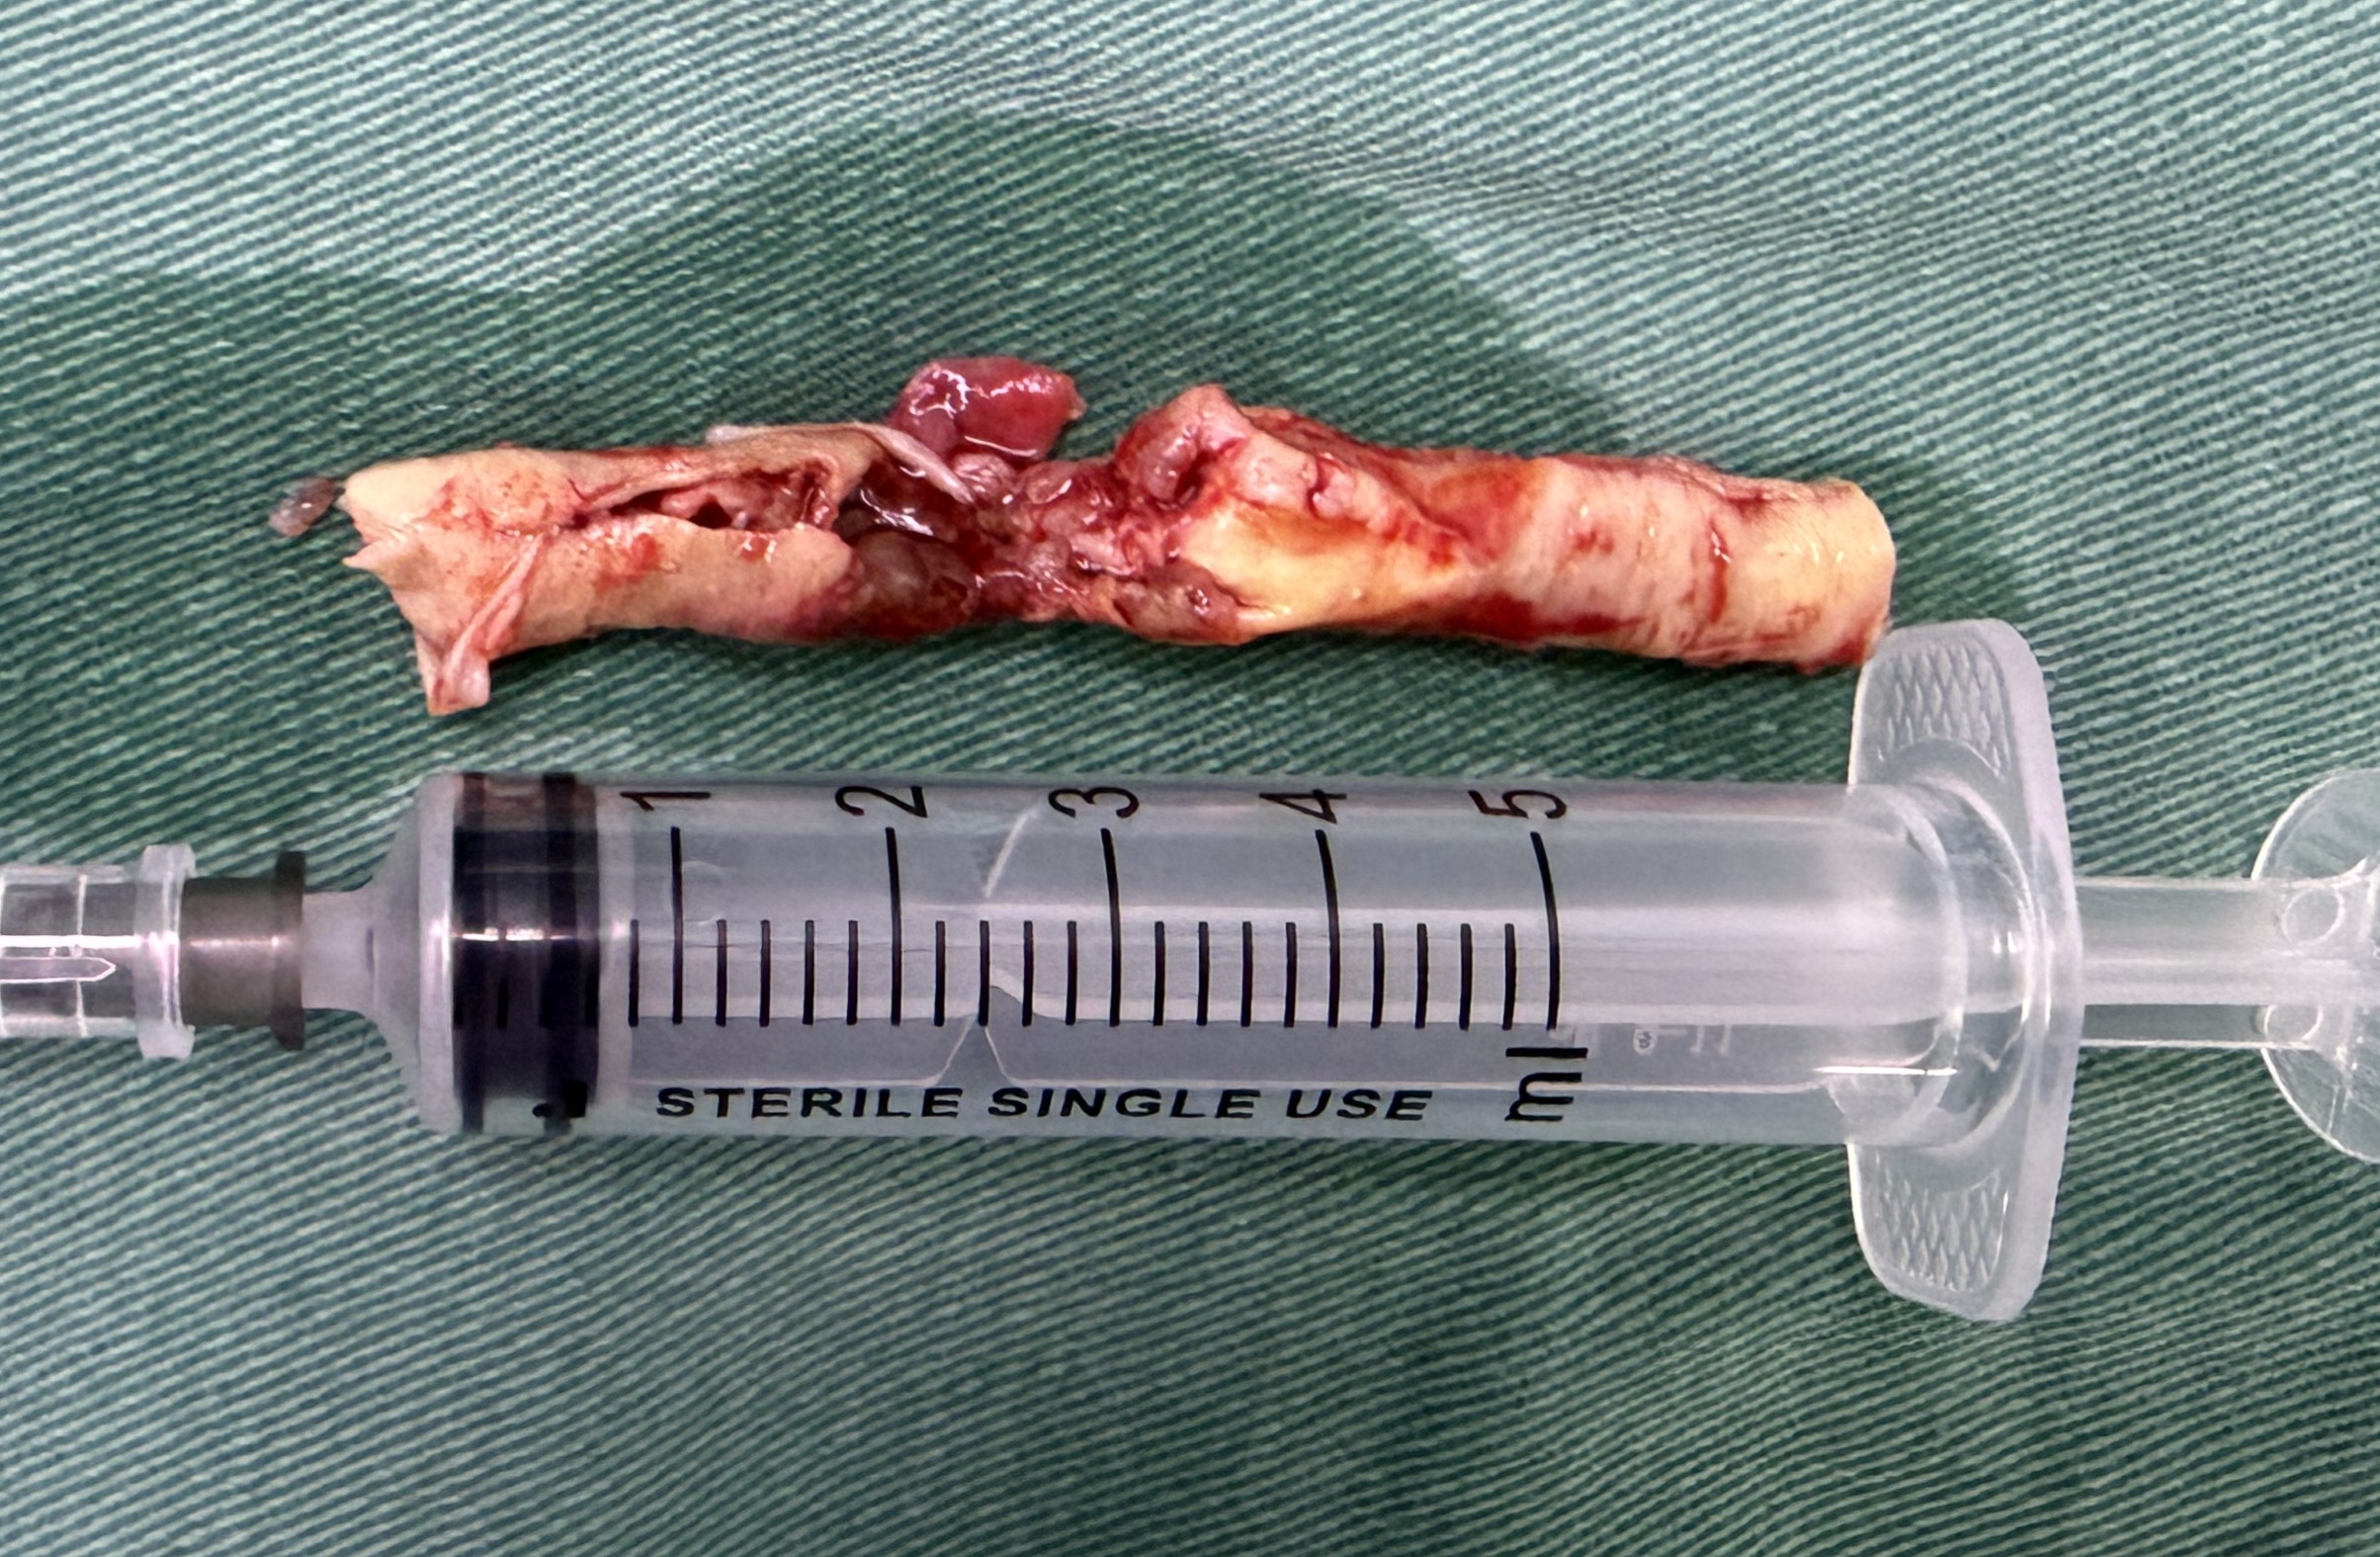

患者为机器碾压导致的复合伤,考虑外伤诱发左侧颈总动脉闭塞,导致多发脑梗死,予以去骨瓣减压手术,病情平稳后,查DSA提示:左侧颈总动脉闭塞,闭塞段位于颈2椎体至颈6椎体之间。和家属充分沟通后,行显微左侧颈动脉开通手术,手术顺利,术后患者症状明显好转,特此分享。